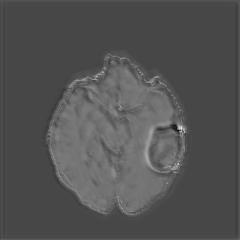

(a) (b) (c) (d)

Boundary Stream:

Fig. 2 demonstrates the output of each of the attention layers in our dedicated boundary stream. In essence, each attention layer progressively localizes the tumor and refines the boundaries. The first attention layer has learned rough estimate of the boundaries around the tumor and localized it, whereas the second and third layers have learned more fine-grained details of the edges and boundaries, refining the localization. Moreover, since our architecture leverages a dilated spatial pyramid pooling to merge the learned feature maps of the regular segmentation stream and the boundary stream, multiscale regional and boundary information have been preserved and fused properly, which has enabled our network to capture the small structural details of the tumor.